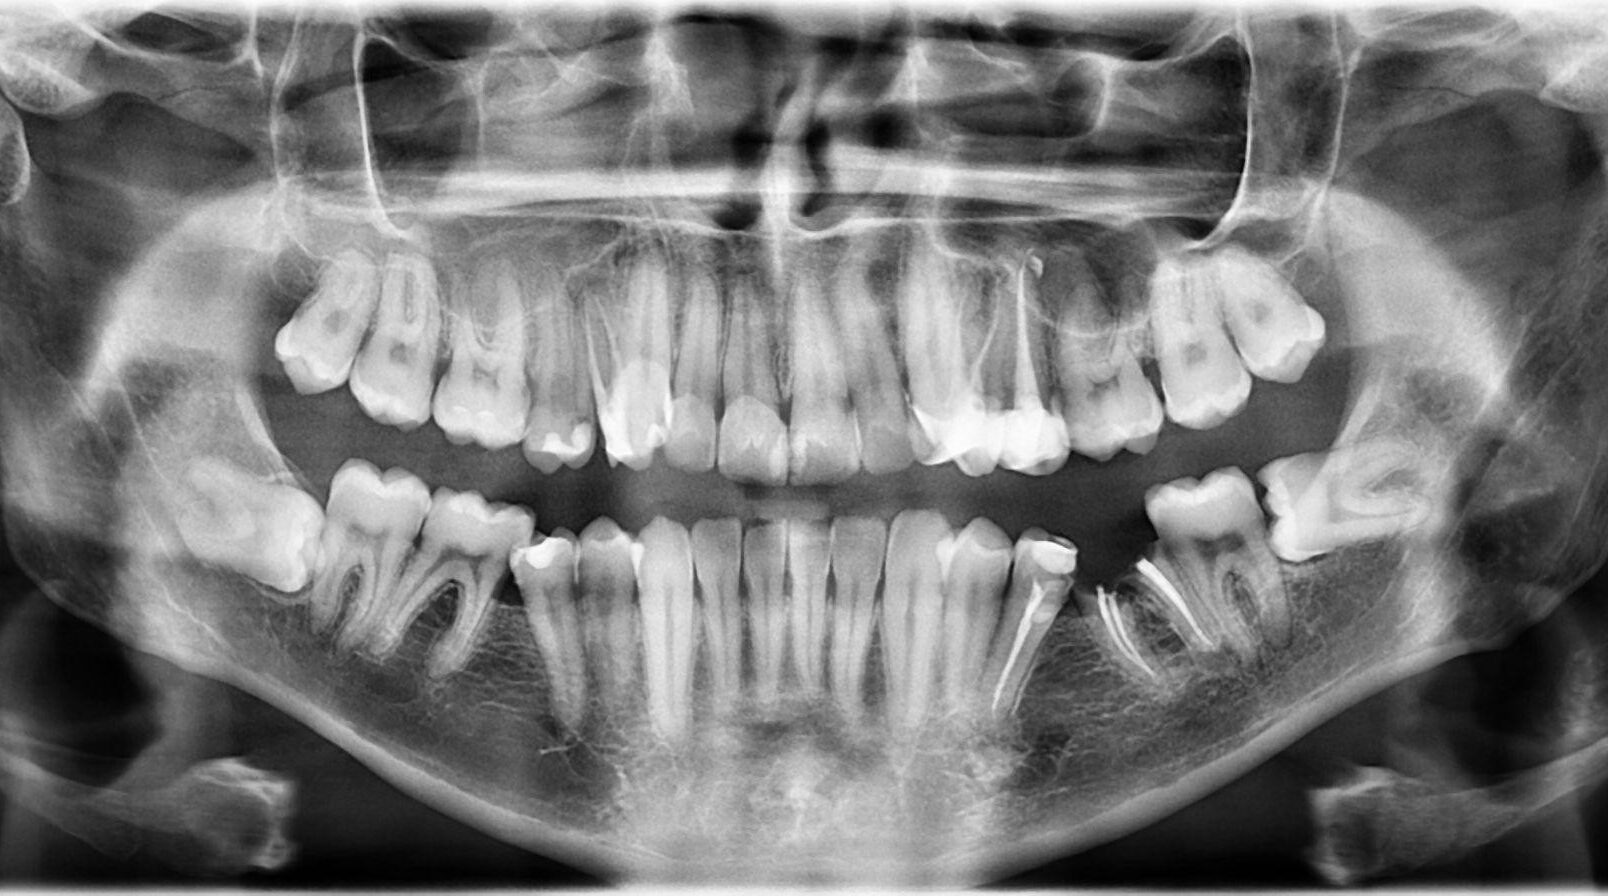

17. What options cannot be selected for this X ray?

18. What option can be selected for radiopacity in the tooth # 4.3 area?

19. What option can be selected for the following X ray?